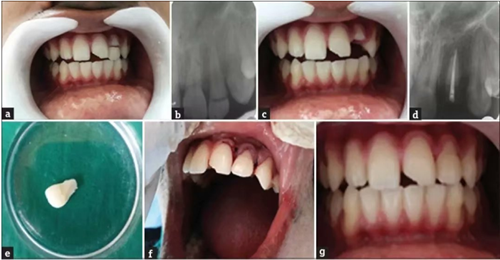

病例1

患者,男,23歲,因跌倒在地導(dǎo)致左側(cè)上頜側(cè)切牙復(fù)雜冠折?;佳罒o明顯松動,口內(nèi)和口外檢查無明顯軟組織創(chuàng)傷。牙齒22出現(xiàn)EllisⅢ級牙折,牙折線從舌側(cè)中1/3至舌側(cè)齦下2mm處。折斷部分松散地附著在牙齒上。

a. 術(shù)前口內(nèi)照片;b. 術(shù)前根尖片;c. 拔除牙齒折斷片;d. 根尖部分充填;e. 牙齒折斷片;f. 折斷片再復(fù)位;g. 軟組織縫合;h. 術(shù)后2年。

根尖片顯示牙根發(fā)育完全,無嵌入?;颊呦MA粞例X,計劃給予患者根管治療和樁核修復(fù)。

局部麻醉后,輕輕去除患牙折斷部分,并放入生理鹽水中防止脫水和變色。仔細(xì)檢查折斷片與患牙的適應(yīng)性。根尖定位儀確定根管工作長度并拍攝根尖片確認(rèn),擴(kuò)孔鉆進(jìn)行根管冠部擴(kuò)大,根管在工作長度上擴(kuò)大到60#。在制備過程中使用約3%的次氯酸鈉沖洗、將根管用指尖干燥并用根管封閉劑封閉,牙膠尖充填根管,根管口臨時修復(fù)體密封。牙髓治療完成后的第二天,局麻下翻瓣,暴露腭側(cè)齦下斷緣。去除根管冠部2/3部分的牙膠,預(yù)備樁道。試?yán)w維樁,并調(diào)到合適的長度。對折斷部分的牙折片髓室部分進(jìn)行預(yù)備以容納纖維樁的冠部及核。然后用37%磷酸酸蝕,沖洗、干燥后涂布粘結(jié)劑。使用雙固化樹脂粘結(jié)劑(RelyX, 3M, )將樁置于根管中,經(jīng)過適當(dāng)?shù)纳{(diào)匹配后,冠部折斷片內(nèi)部進(jìn)行酸蝕并用可流動復(fù)合樹脂粘結(jié)到牙齒上。最后,皮瓣復(fù)位,縫合,檢查咬合并給予患者術(shù)后指導(dǎo)。術(shù)后1月,3月,6月,1年,2年進(jìn)行臨床和影響學(xué)檢查,牙齒愈合良好。